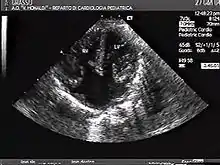

Atrioventricular canal defect is a combination of abnormalities of the heart and is present at birth. There is a problem when there are holes present in the walls that separate chambers (septa), as well as when valves are incorrectly constructed. There are other names for these heart abnormalities such as endocardial cushion defects or atrioventricular septal defect[4]

Atrioventricular canal defect may be divided into partial or complete forms. In the partial form, openings between the left and right atria and improper formation of the mitral valve exist. In the complete form, there is free movement in all chambers because there is a large hole where the atria and ventricles meet, and instead of there being two valves there is one common valve.[4]